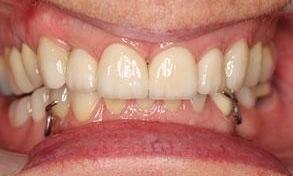

This before and after showcases a comprehensive dental restoration involving root canal therapy, the placement of dental crowns for structural integrity and aesthetics, as well as a full upper denture to restore function and appearance.